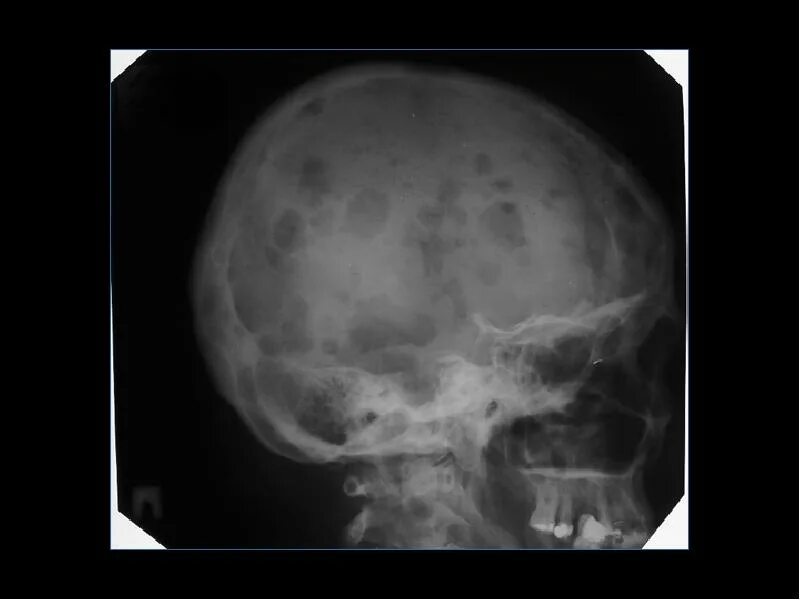

Лучевая диагностика доброкачественных